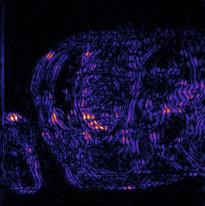

Recently, deep neural networks have greatly advanced undersampled Magnetic Resonance Image (MRI) reconstruction, wherein most studies follow the one-anatomy-one-network fashion, i.e., each expert network is trained and evaluated for a specific anatomy. Apart from inefficiency in training multiple independent models, such convention ignores the shared de-aliasing knowledge across various anatomies which can benefit each other. To explore the shared knowledge, one naive way is to combine all the data from various anatomies to train an all-round network. Unfortunately, despite the existence of the shared de-aliasing knowledge, we reveal that the exclusive knowledge across different anatomies can deteriorate specific reconstruction targets, yielding overall performance degradation. Observing this, in this study, we present a novel deep MRI reconstruction framework with both anatomy-shared and anatomy-specific parameterized learners, aiming to "seek common ground while reserving differences" across different anatomies.Particularly, the primary anatomy-shared learners are exposed to different anatomies to model flourishing shared knowledge, while the efficient anatomy-specific learners are trained with their target anatomy for exclusive knowledge. Four different implementations of anatomy-specific learners are presented and explored on the top of our framework in two MRI reconstruction networks. Comprehensive experiments on brain, knee and cardiac MRI datasets demonstrate that three of these learners are able to enhance reconstruction performance via multiple anatomy collaborative learning.